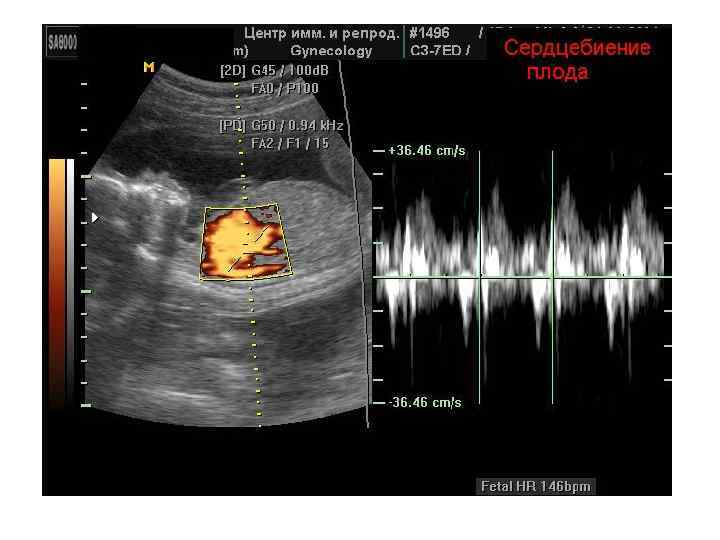

Импульсный допплер (PW, HFPW) • • На временной развертке по вертикали отображается скорость потока в исследуемой точке. Потоки, которые двигаются к датчику отображаются выше базовой линии, обратный кровоток (от датчика) - ниже.

Импульсный допплер (PW, HFPW) • • На временной развертке по вертикали отображается скорость потока в исследуемой точке. Потоки, которые двигаются к датчику отображаются выше базовой линии, обратный кровоток (от датчика) - ниже.